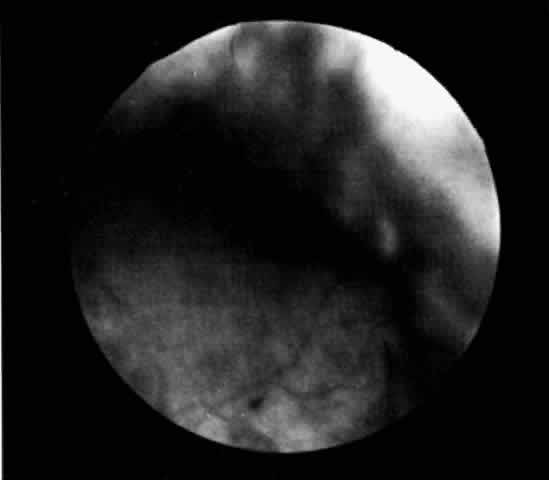

Ciliochoroidal effusions may have an annular, lobular (Fig. 4), or flat (Fig. 5) ophthalmoscopic appearance. Annular effusions occur around the ciliary body and peripheral choroid. Lobular effusions are large hemispheric detachments that bulge toward the center of the globe. Flat effusions are most often apparent in isolated peripheral choroidal areas, where local structures limit fluid extension. A local stimulus, such as a limbal incision, can lead to suprachoroidal edema, even in remote areas, by way of free dissection of fluid. Occasionally, patients will present with coexisting ciliochoroidal effusion and rhegmatogenous retinal detachment.23–25 The retinal hole may be hidden in the choroidal mounds. Such detachments tend to occur in older patients who have a history of previous ocular surgery.

Fig. 4. Clinical appearance of a lobular type of ciliochoroidal effusion.